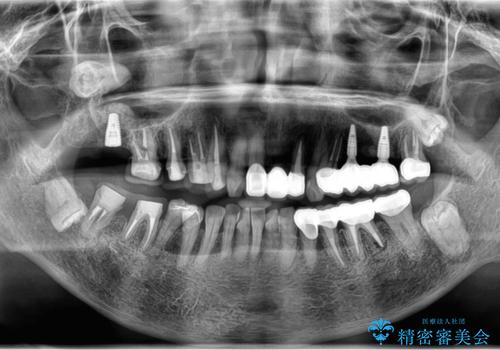

- 見た目の悪い銀歯や虫歯、歯の欠損、全体的な治療を希望されて来院されました。

インプラント治療や根管治療・セラミック治療を総合的に考えた精度の高い治療を計画し、しっかり噛めるようになるのはもちろん長期的な予後や審美性の向上を考えた全顎的な治療を実践していきます。

期間は約2年ほどかかりましたが、審美的な仕上がりとともに清掃のしやすさも非常に満足いただくことができました。